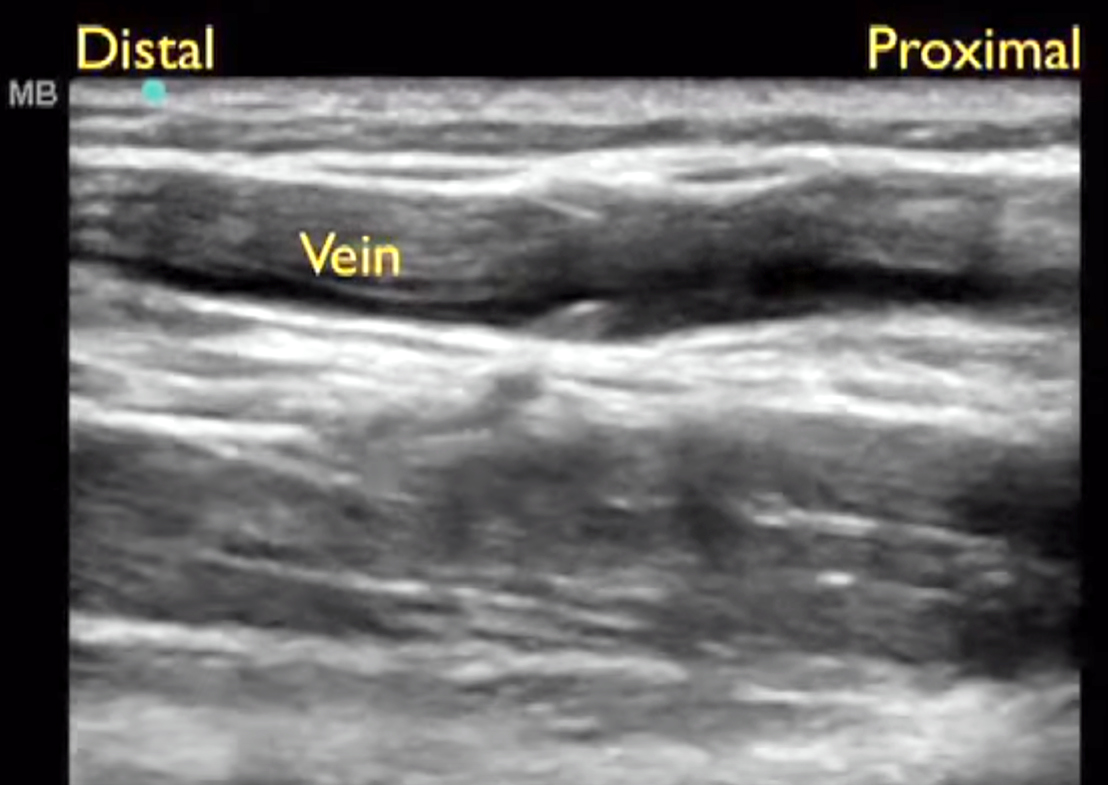

- En el eje longitudinal la vena basílica se visualiza como una estructura alargada en la parte superior de la imagen ecográfica.

Imagen proyección longitudinal vena basílica: